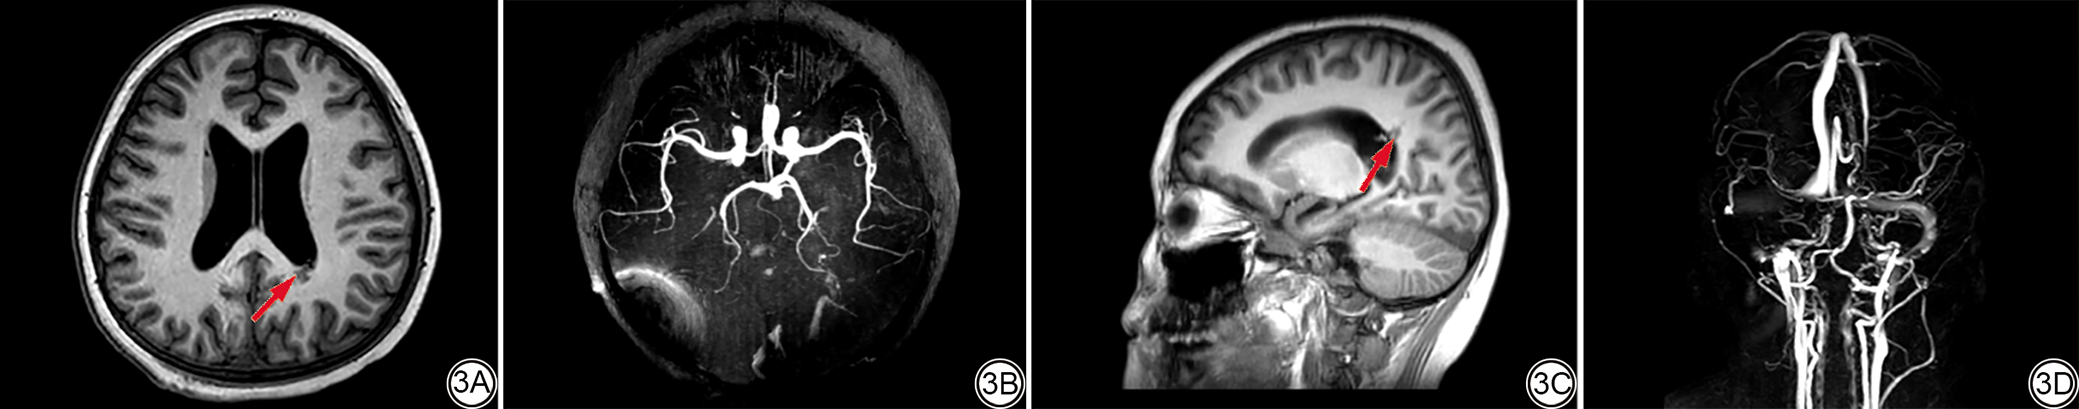

统计分析发现,不同类型的CVMs的检出情况在DSA、CTA、MRA及CTA联合MRA之间差异无统计学意义(χ2=4.626,P=0.969)。而与DSA(图1)相比,CTA、MRA单独检测检出CVMs的数量(34/38、33/38)低于DSA,差异具有统计学意义(P<0.05),而CTA与MRA联合诊断检出CVMs的数量(40/38)与DSA接近,差异无统计学意义(P>0.05)(表1)。典型病例的DSA图像、CTA图像和MRA图像分别见图1, 图2, 图3

图2  CT平扫及CTA的VR成像立体图。男,11岁,因脑出血入院,确诊为脑动静脉畸形。2A:CT平扫显示右侧枕部见引流管影,左侧脑室后角见畸形血管影(红箭)。2B:CTA的VR立体成像,显示直窦血管稍粗,左侧横窦见增粗引流静脉影(红箭)。CT:计算机断层扫描;CTA:CT血管造影;VR:虚拟现实。

Fig. 2  Plain CT and VR imaging of CTA. Male, 11 years old, admitted to the hospital due to cerebral hemorrhage and diagnosed with cerebral arteriovenous malformation. 2A: The CT plain scan shows a drainage tube shadow in the right occipital region and a malformed blood vessel shadow in the posterior horn of the left ventricle (red arrow). 2B: The VR stereoscopic imaging of CTA shows that the blood vessels in the straight sinus are slightly thickened, and there is a thickened draining vein shadow in the left transverse sinus (red arrow). CT: computed tomography. CTA: computed tomography angiography. VR: virtual reality.